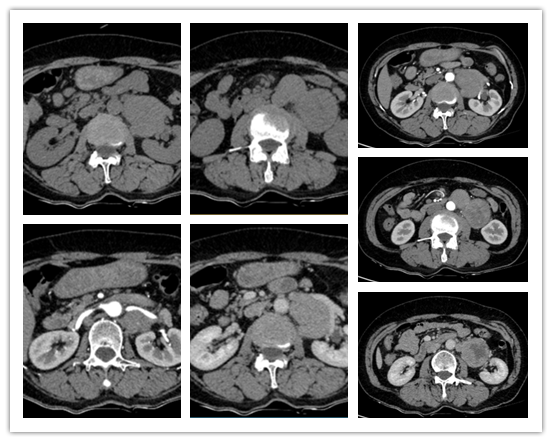

患者二,女性,57岁。因“体检发现左肾门附近占位病变1月余”入院。当地医院CT示左肾门下端占位,考虑巨淋巴细胞增生症,不排除淋巴瘤可能,大小约8.0*4.5*5.5cm,合并左侧附件区阔韧带肌瘤。入院后完善相关检查及化验,RAAS系统及儿茶酚胺类化验未见明显异常。CT显示腹主动脉旁软组织影,密度不均,中央斑片状低密度影,大小约10.1*6.0*5.2cm,呈不均匀中度强化,多考虑后腹膜肉瘤并淋巴结转移,转移瘤不除外。术前经相关检查及专家讨论后,明确诊断为腹膜后肿瘤,遂为患者实施了腹膜后肿瘤切除术。手术历时约3小时,患者术后恢复良好,继续开展进一步治疗。